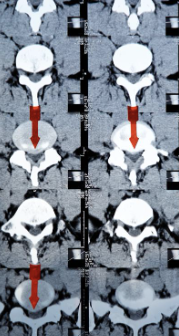

허리디스크 증상 치료방법 및 수술비용에 대해 알아보겠습니다. 허리디스크는 척추 뼈 사이에 있는 디스크가 손상되어 신경을 압박하는 질환입니다. 디스크는 척추뼈 사이의 충격을 흡수하고 척추의 움직임을 부드럽게 해주는 역할을 하는데, 이 디스크가 손상되면 신경을 압박하여 통증, 마비, 감각 이상 등의 증상이 나타납니다. 허리디스크는 흔히 40~50대 중년층에서 발생하지만, 젊은 나이에도 발생할 수 있습니다.

4. 신경 압박: 허리디스크는 주변 척추 신경을 압박하여 신경 압박 또는 충돌과 같은 상태를 유발할 수 있습니다. 이로 인해 바늘로 쏘이는 듯한 통증, 찌릿한 통증 또는 영향을 받는 신경 경로를 따라 감각 상실과 같은 증상이 나타날 수 있습니다.